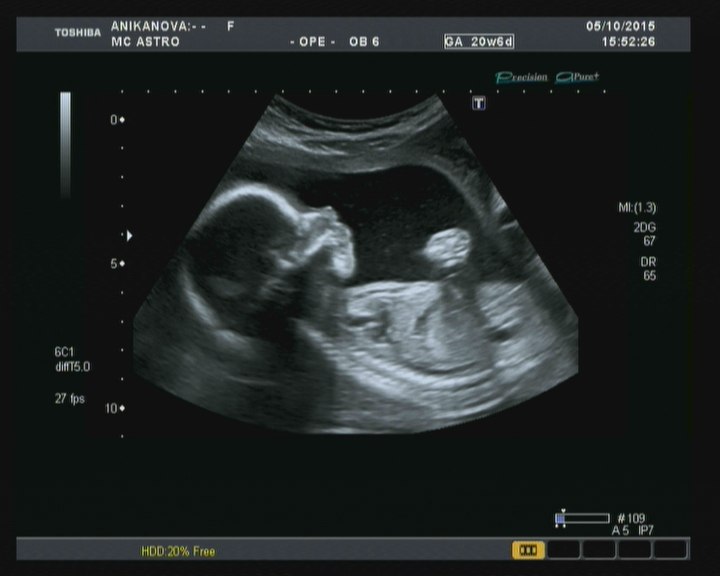

Мои неделькиСегодня ходили на УЗИ. Все отлично, только по размерам, как и в 12 нед. на неделю меньше срок ставят. И вот 21 неделе мой кружок порозовел. У нас снова будет маленькая козявка. Папа наш очень хотел братика Мире, даже немного расстроился. Тем более пдр в р-не 23 февраля))))) Боится не справиться с нашим бабьим царством.

Маленький человечек